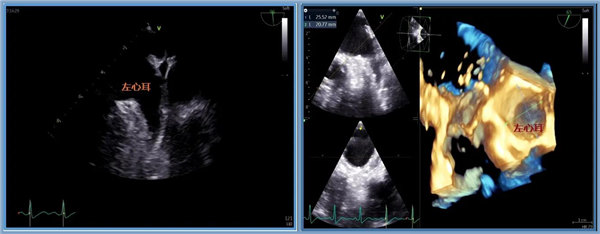

患者何先生今年50多岁,因阵发性房颤收入我院心内科,其阵发性房颤诊断明确,需要接受房颤射频消融手术。术前需要做经食道超声心动图检查,以排除左心耳血栓等禁忌症。经心内科和超声科充分评估患者病情,获得患者知情同意后,充分术前准备,9月1日下午,在上级医生的指导下,超声科李炜明主治医师顺利完成我院首例经食道超声心动图检查。整个检查全程耗时不到10分钟,患者无明显不适,安返病房。检查结果明确排除左心耳血栓,为患者即将进行房颤射频消融手术排除风险。

二维和三维清晰显示左心耳

据了解,经食道超声心动图检查是利用安装在像胃镜一样的超声探头,通过患者口咽部深入到食道、胃部,放置到心脏的后方来对心脏进行检查。这样的检查图像更加清晰,解剖结构更加清楚,病变诊断更加准确,而且能显示经胸无法检查的结构如左心耳等,对心脏手术的术前评估和术中监测有不可替代的作用,被誉为探查心脏的“火眼金睛”。